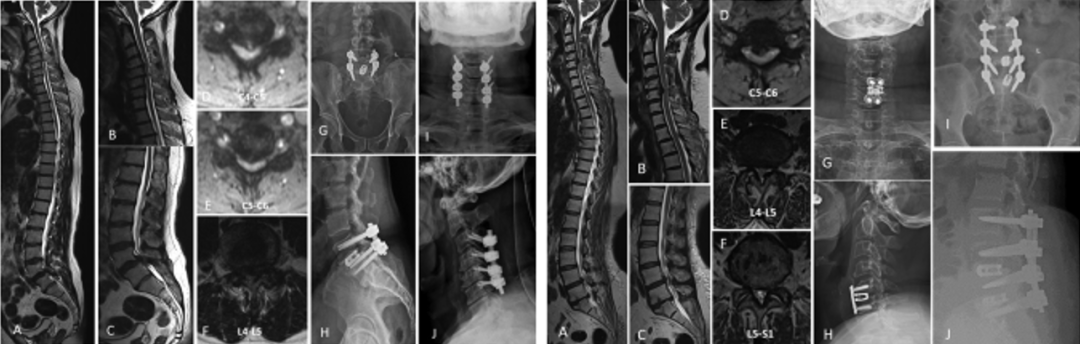

A型:颈腰椎型,CL-TSS,分为4个亚型

A1型-有颈脊髓症状,但没有腰椎症状。

A2型-有腰椎症状,但没有颈脊髓症状。

A3型-有腰椎症状,没有颈脊髓症状,但有影像学改变。

A4型-同时有颈脊髓症状和腰椎症状。

对238例手术患者进行分类,A型186例、B型11例、C型24例和D型17例。A型中A1型58例,A2型97例,A3型7例,A4型24例。B型中B1型6例,B2型5例。C型中C1型20例,C2型4例。所有患者都随访至少2年。患者的平均年龄为62.17±10.91岁,男女比为3:1。

随访结果显示,A1型术前平均Nurick分级从3.8±0.98改善至最终随访时的1.74±0.74,期间仅11例(19%)患者需要另行腰椎减压,平均间隔为8.2个月;A2型平均ODI评分从40.7±13.8改善至15.1±4.8,只有4例患者(4.1%)在期间出现新的脊髓病症状,并接受了颈椎手术,平均间隔为8.8个月;A3型因症状的发展理论上都需要进行二次减压,但出于患者意愿,仅有5例患者(71.4%)另行颈椎减压术,平均间隔8.9个月;A4型有12例患者(50%)接受了分期减压,手术平均间隔为6.9个月。